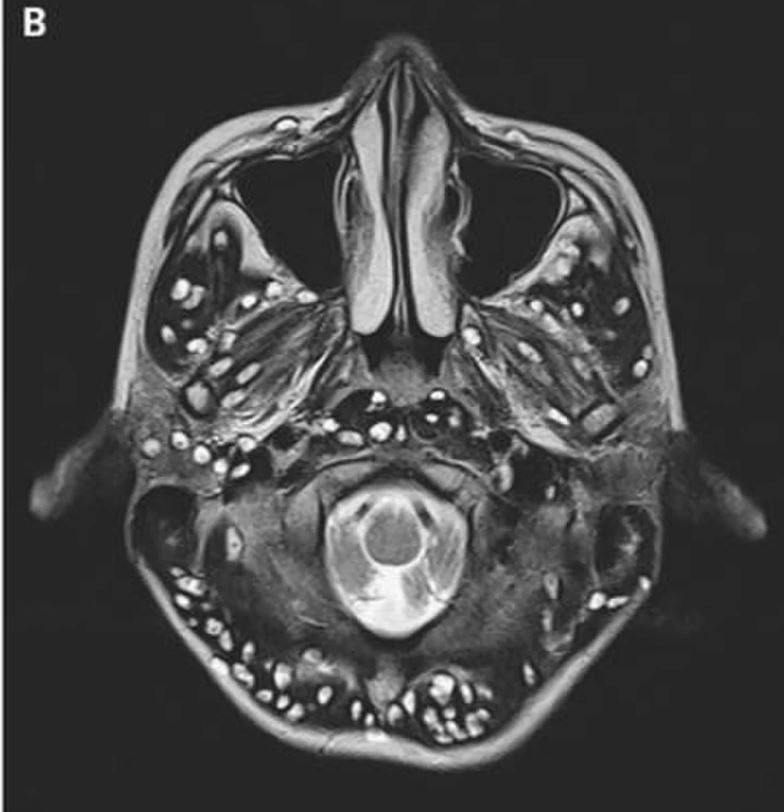

That’s when an MRI revealed cerebral cortex and brain-stem damage caused by cysts. He was diagnosed with neurocysticercosis, which is caused by ingesting tapeworm eggs that have passed in the feces of someone with an intestinal tapeworm.

The larvae wiggle out of their eggs and find a home in muscle and brain tissues, where they form cysts. They were also discovered in the patient’s right testicle and eye.